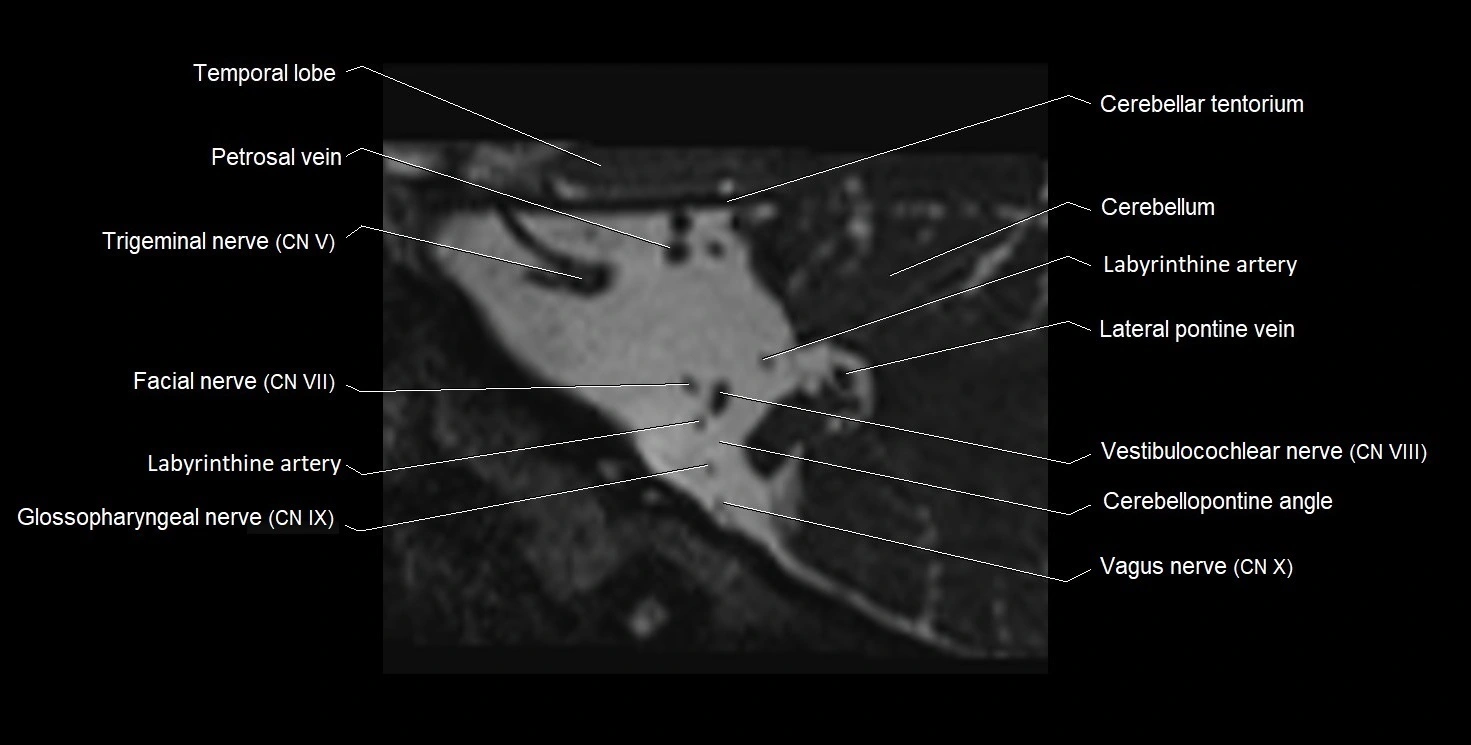

MRI images

image